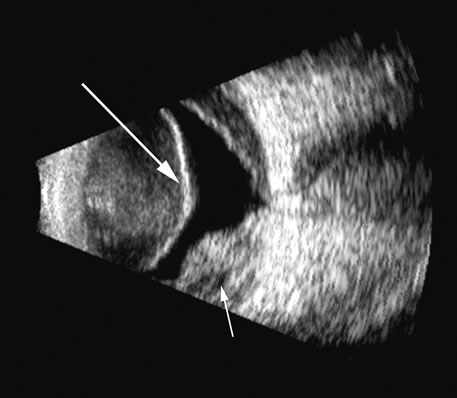

Malignant melanoma varies in its ultrasound presentation from a relatively homogeneous to heterogenous lesion on B-scan. The typical uveal melanoma absorbs sound so that the posterior section is relatively less echoic than the anterior aspect, producing a gradually decreasing amplitude, often to baseline on the A-scan (Fig. 21).

Melanomas also have varying amounts of melanin, a highly acoustically reflective pigment. As noted, melanomas characteristically show high reflectivity anteriorly, with decreasing reflectance as the sound traverses the tissue. This produces the decreasing amplitude posteriorly in the tumor seen on A-scan and gray-scale B-scan. This effect often enhances the anterior scleral boundary. The posterior tumor border is thus measured as the first “rising” echo from the tumor decline, and it is most easily seen and accurately identified on B-scan.27 Metastatic carcinoma is more heterogeneous, producing a more uniform A-scan amplitude of roughly 50% to 80% of the “scleral” echo amplitude (see below) behind the tumor (Fig. 22). Hemangioma is a very highly reflective tumor with high amplitude all the way through the tumor of 80% to 100% of scleral echo amplitude (Fig. 23). The differentiation of tumor tissues is made possible by differences in cellular organization and concentration.29 Acoustically, these are termed as differences in backscattering properties.30–32 A homogeneous solid tissue, such as the lens or the optic nerve, may present few or no echogenic discontinuities and thus appear anechoic and cyst-like. (An echogenic discontinuity is technically an acoustic impedance mismatch in which the acoustic impedance is the product of the density and the speed of sound in each tissue.) A fluid–smooth tissue boundary has a high mismatch or discontinuity and thus produces a high-amplitude echo. A hemangioma with alternating blood- and tissue-lined sacs thus produces a solid-appearing tissue with high-amplitude echoes seen at all depths of the tissue. A metastatic tumor is nearly always a very heterogeneous tissue with randomly organized clumps of similar cells bounded by strands of vessels, necrotic areas, and connective tissue, thus producing a pattern of moderately high-amplitude sustained echoes. To provide a meaningful, reproducible standard of comparison, we use the scleral echo—that is, an echo behind the tumor—for comparison. We believe that the scleral echo generally is highest at the posterior sclera–Tenon's boundary; whereas Ossoinig has stated that the high amplitude echo is at the anterior scleral boundary.28,33 This school (standardized echography) also recommends a tissue velocity for melanoma of 1550 m/sec34,35 compared with the value of 1660 m/sec that we recommend. These differences can produce significant variations in measurement of tumor height, depending on the interpretive methodology used. The velocity of 1550 m/sec gives a smaller tumor height than that of 1660 m/sec, wheras the inclusion of scleral thickness may add 1 to 2 mm to the tumor height when standard echography is used. While this does not affect comparisons of tumor growth, it has a significant bearing on comparisons of data from various investigators.27 On B-scan, the invasion or replacement of the choroid by tumor is of diagnostic importance. Subretinal hemorrhage rests on a smooth curve of the posterior poles; whereas melanoma may replace the choroid, producing an “excavated” pattern.36 A completely dislocated lens can also emulate a tumor but can be differentiated by clinical findings and by having the patient move his or her eye during the examination, which causes lens displacement (Fig. 24).